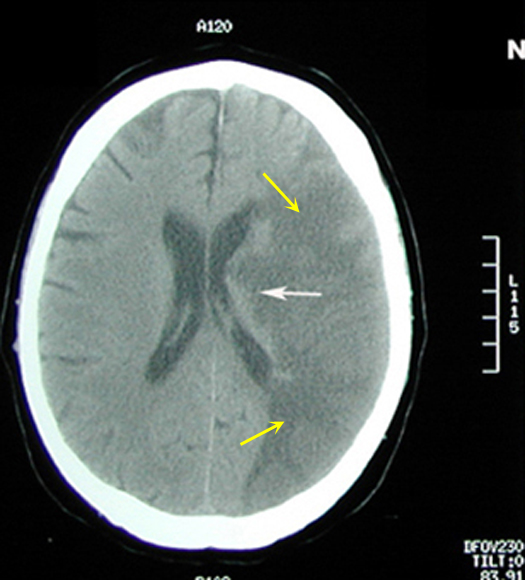

Figure 1: Non-contrast axial CT brain

Imaging findings: Figure 1

- Large area of low CT attenuation (hypodense) is seen involving the left middle cerebral artery distribution (yellow arrows), with involvement of both gray and white matter.

- White arrows points to involvement of basal ganglia region with infarction also.

- Gyri and sulci are effaced on the left side (compare to normal right side).